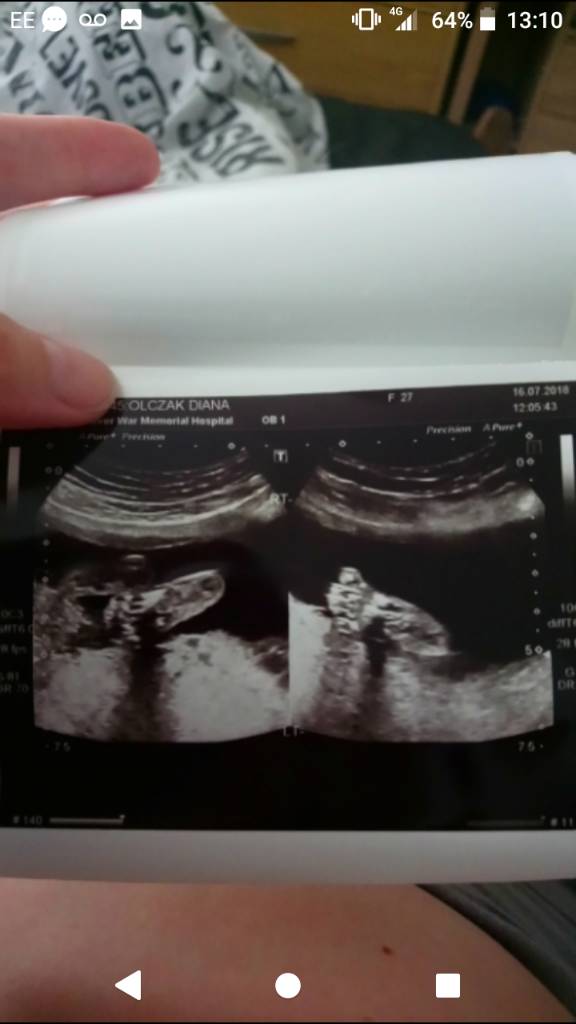

My też już po usg

Mały dalej jest chłopcem, bez najmniejszej szansy na pomyłkę

Mały dość ruchliwy na usg, cały czas glasial się po buzi I wciska kciuka w usta, odkopywal głowice jak lekarka za mocno docisnela żeby coś pomierzyć

Zobacz załącznik 878092Zobacz załącznik 878093